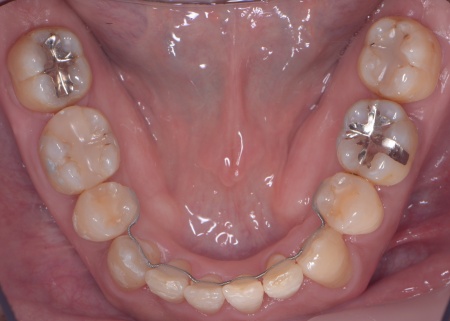

40代男性 乱れた歯並びと重度歯周病をワイヤー矯正と歯周再生療法で治療した症例

拝見したところ、上下の歯は、ずれたりねじれたりしてデコボコに生えており、著しく歯並びが乱れていました。

またレントゲン撮影をして確認すると、右上前歯は顎の骨の中に埋まっている骨性埋伏(こっせいまいふく)の状態でした。

さらに、左下奥歯は重度の歯周病であり、歯を支えている骨が一部溶けていることが判明しました。

以上のことから、歯並びを整える矯正治療と歯周病の治療を併せて行う必要があると診断しました。